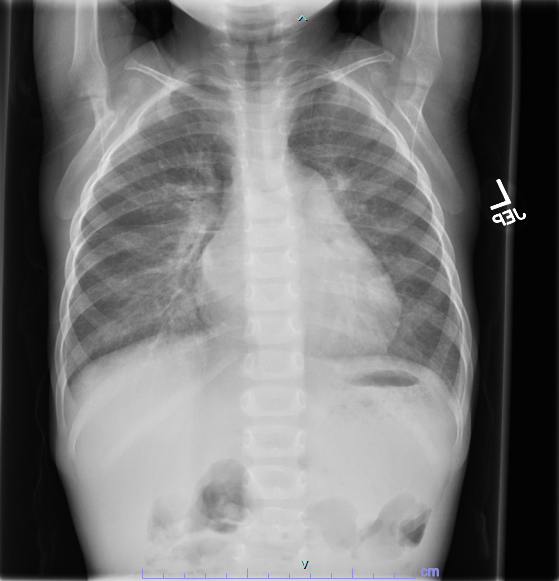

Due to FTT diagnosis, gastroenterology was consulted. Testing for food intolerances and malabsorptive processes was initiated which was unrevealing. He had 1.5kg weight gain over three days and developed facial edema, hepatomegaly and tachypnea, so IV fluids were discontinued. Chest x-ray showed pulmonary venous congestion, ECG revealed possible left atrial enlargement, and BNP was elevated at 2,286 pg/mL. Echocardiogram revealed cor triatriatum sinistrum. Pediatric cardiology was consulted, and the patient was diuresed with furosemide. After reaching euvolemia, he was discharged home and followed closely. He underwent surgical resection of left atrial membrane. Post-operative course was uncomplicated and FTT resolved.

CTS may present at nearly any age, with cases of more severe obstruction presenting during infancy. Typical presenting symptoms include activity intolerance, cyanosis, respiratory distress, murmur, and cardiogenic shock. In this case the pulmonary venous congestion resulted in symptoms of tachypnea and FTT more commonly seen with pulmonary over circulation in left to right shunts such as ventricular septal defects. Diagnosis may be made with transthoracic echocardiography.